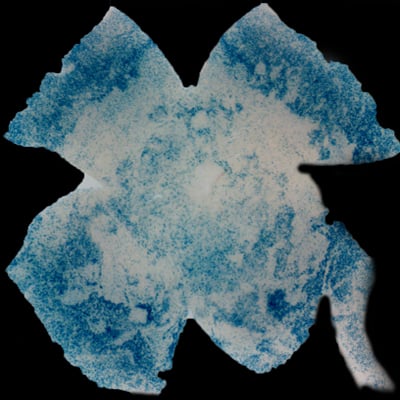

| Insulin affects cone survival in Retinitis Pigmentosa. Shown is a retinal flat mount of an rd1 mutant showing surviving cones at 7 weeks of age in blue (left panel). The rd1 mutant is part of the Retinitis Pigmentosa family of RD diseases. Rollover image to see normal cone distribution at 3 weeks of age in the same mutant before the onset of cone death. To the right is an image of a retinal flat mount at 7 weeks of age of an rd1 mutant treated for 4 weeks with daily injections of insulin showing an increased number of surviving cones. Rollover image to see what happens when endogenous insulin is removed for the same period of time. | |

Our recent studies on Retinitis Pigementosa have led us to propose that cone death is preceded by metabolic changes in cone photoreceptors and that cones die due to nutrient deprivation, in particular glucose. This hypothesis was based on gene expression changes seen at the onset of cone death in many gene that are involved in cell metabolism in addition to gene expression changes in genes that belong to the Insulin/mTOR signaling pathway. This signaling pathway is a key pathway in regulating cellular metabolism. As a proof of concept we injected mice systemically with insulin for a period of 4 weeks to test if stimulation of the pathway could improve cone survival (Figure to the right). The positive outcome of our insulin treatment reinforced our hypothesis. However, contrary to the regular action of insulin in muscle, liver and adipose tissue, where it enhances glucose uptake from the blood by release of the glucose transporter 4 to the cell membrane, the action of insulin on the retina improved glucose metabolism by changing the expression of various glycolytic genes that are regulated by the insulin/mTOR pathway.